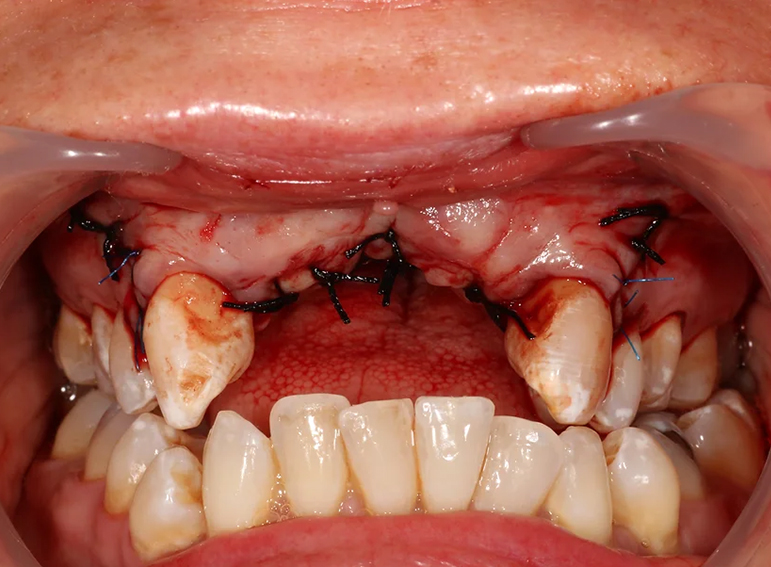

Oral rehabilitation after a road traffic accident.